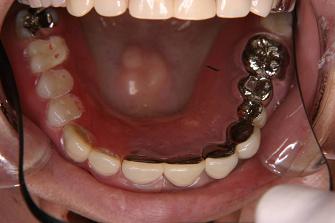

2. 作製したバネなし入れ歯

(バルプラスト)です

裏側